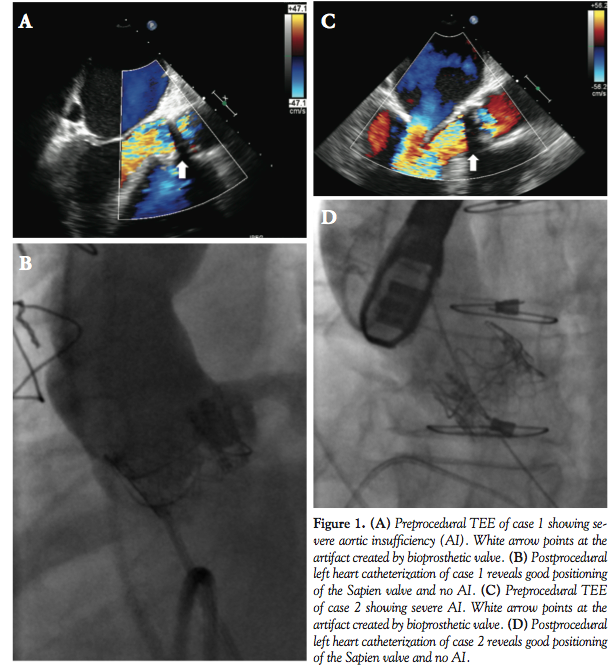

He was deemed to be a high-risk candidate for any surgical intervention due to his critical state (logistic EuroSCORE of 56%, EuroSCORE II of 41.1%), re-do sternotomy, and extensive chest wall collaterals from prior coarctation. After careful review by a multidisciplinary team, the patient was considered for valve-in-valve TAVR. He underwent expedited TAVR evaluation with peripheral and coronary angiography immediately prior to valve replacement. Using transesophageal echocardiogram (TEE; Figure 1A) and aortic root angiography, a 26 mm Edwards Sapien was chosen and successfully deployed via transfemoral approach. The pulmonary artery systolic pressure (PAPs) dropped from 75 to 40 mm Hg following intervention. The procedure was complicated by high-grade atrioventricular block requiring permanent pacemaker placement. Follow-up imaging demonstrated no significant residual transvalvular or perivalvular AI (Figure 1B). He was discharged 14 days after the procedure. At 4-month follow-up exam, the patient’s condition was much improved, with minimal heart failure symptoms and restored renal and liver function.

s/p bioprosthetic aortic valve replacement and 5-vessel coronary artery bypass in 1999 presented to an outside hospital with acute onset of chest pain and shortness of breath. He was diagnosed with an acute non-ST elevation myocardial infarction. Coronary angiogram demonstrated patent bypass graft and severe aortic regurgitation due to degenerative and failing bioprosthesis. This was confirmed by TEE (Figure 1C). The initial ejection fraction was estimated to be 45%.

Due to his comorbidities, re-do sternotomy, and frailty, he was considered to have prohibitive risk for surgical aortic valve replacement (logistic EuroSCORE of 82.1%, EuroSCORE II of 52.6%) and was transferred to our institution to be considered for TAVR. Within 12 hours from transfer, the patient’s condition quickly deteriorated with refractory hypotension, high-grade atrioventricular block, and asystole. The patient received 20 minutes of cardiopulmonary resuscitation and emergent temporary transvenous pacemaker. Due to his tenuous status and high surgical risk, he was considered for compassion use of TAVR. He also had expedited TAVR evaluation with peripheral angiography immediately prior to procedure. He underwent successful TAVR with a 23 mm Sapien valve via transfemoral approach. Intraoperative TEE demonstrated no valvular AI and trace paravalvular leak. The PAPs dropped from 76 to 34 mm Hg following intervention. Due to persistent high-grade atrioventricular block, a permanent pacemaker was placed. There was resolution of heart failure symptoms (Figure 1D) and the patient was discharged from the hospital 5 days after the procedure.